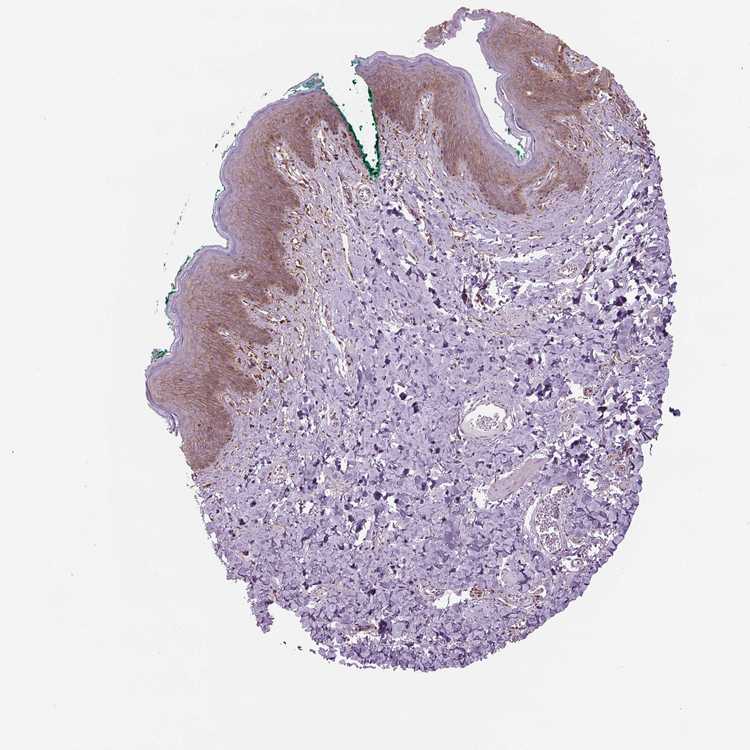

SKIN 1 - Antibody stainingi

Antibody staining in the annotated cell types in the current human tissue is reported as not detected, low, medium, or high, based on conventional immunohistochemistry profiling in selected tissues. This score is based on the combination of the staining intensity and fraction of stained cells.

Each image is clickable and will lead to virtual microscopy that enables deeper exploration of all samples and also displays staining intensity scores, fraction scores and subcellular localization as well as patient and tissue information for each sample.

Antibody HPA067595Antibody HPA069443Antibody CAB022062

Langerhans -Not detectedMedium

Cells in basal layer High--

Cells in corneal layer Not detected--

Cells in granular layer Not detected--

Cells in spinous layer Not detected--

Endothelial cells Not detected--

Extracellular matrix Not detected--

Fibroblasts -HighHigh

Fibrohistiocytic cells High--

Hair follicles High--

Keratinocytes -Not detectedMedium

Langerhans cells Not detected--

Lymphocytes Not detected--

Melanocytes HighHighHigh

Sebaceous glands High--

Vascular mural cells Not detected--